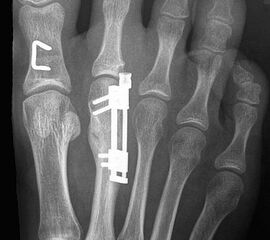

Das im Folgenden vorgestellte Operationsverfahren beschreibt die Kallusdistraktion von Metatarsalia nach den Prinzipien von Ilisarov 21 unter Verwendung eines internen, winkelstabilen Titan-Minifixateur (Klauser 2009). Der interne Distraktor ermöglicht während der Distraktions- und der Durchbauungsphase aufgrund seiner hohen Stabilität je nach Modell (18 mm, 23 mm) eine Verlängerung von bis zu 25 mm. Nach interner Anlage des Minifixateurs, meist lateral, kann über eine kontinuierliche Kallusdistraktion der Metatarsalebogen unter frühzeitiger Mobilisation im Gips oder Short-Walker rekonstruiert werden 15. Über einen interdigital und transcutan ausgeleiteten Aktivatorstab wird die Distraktion vom Patienten selber täglich morgens und abends durchgeführt. Zusätzlich vorliegende Strahlpathologien, wie zum Beispiel eine verkürzte Strecksehne oder ein kontraktes Metatarsophalangealgelenk können im Rahmen der Erstoperation ebenso therapiert werden wie z.B. ein Hallux valgus, ein Hallux valgus interphalangeus und/oder ein Digitus quintus varus (Klauser 2009). Nach Rekonstruktion des Metatarsalebogens wird in einem zweiten, kleinen Eingriff der Aktivatorstab über eine Spezialpinzette diskonnektiert und entfernt, wobei der Distraktor als interne Fixation belassen wird. Die Entfernung des Distraktors erfolgt in der Regel nach 9 – 12 Monaten, da es sich meist um angeborene kindliche Fehlbildungen handelt (Brachymetatarsie) und eine operative Intervention frühzeitig im Kindesalter erfolgen sollte (Klauser 2009).

• Dritter Eingriff: Materialentfernung (Minifixateur interne) bei vollständiger knöcherner Durchbauung, hierbei ist in seltenen Fällen eine Lösung von Verklebungen der Strecksehnen und des Metatarsophalangealgelenks erforderlich.

Meist kam ein 18mm Minifixateur zur Anwendung und ausnahmslos wurde er lateral am Metatarsale implantiert. Bis auf das Metatarsale 5 wurden vom Autor alle weiteren Metatarsalia (MT1 – MT4) isoliert oder kombiniert verlängert. In 7 Fällen wurde eine simultane Verlängerung zweier Metatarsalia (2x MT1 und MT4, 4x MT3 und MT4, 1x MT2 und MT3) vorgenommen. Bei einem Großteil der Patienten musste eine Strecksehnenverlängerung entweder im Rahmen der Erstoperation oder im Rahmen der Aktivatorentkopplung vorgenommen werden. In neun Fällen (ausnahmslos bei Erwachsenen > 30 Jahre) sogar 2x sowohl während des Erst- als auch Zweiteingriffes. Annähernd regelhaft sind bei den eben genannten Eingriffen Arthrolysen des Metatarsophalangealgelenks des betroffenen Zehenstrahls erforderlich, da durch die Distraktionsverlängerung eine hohe Kompression auf das jeweilige Grundgelenk entsteht.